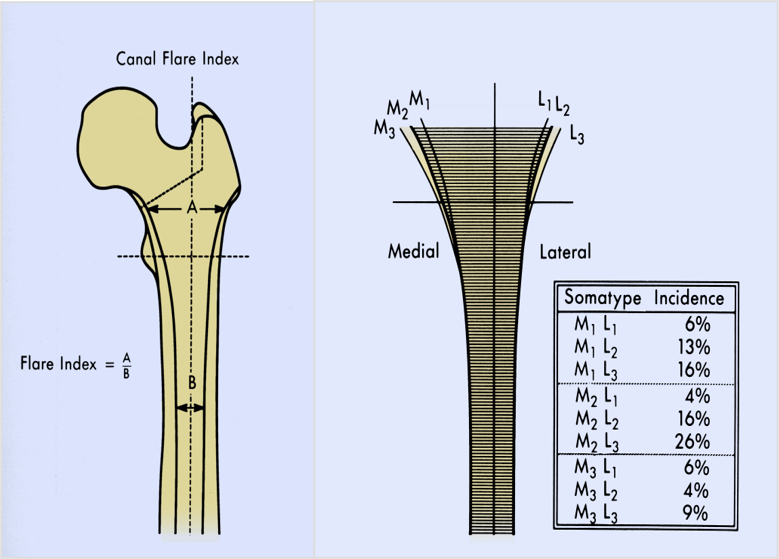

股骨近端髓腔类型与柄的选择

- Dorr分类法

- TypeA型:股骨髓腔在正位片上显示较厚的内外侧皮质,在侧位上显示较厚的后侧皮质,远端股骨髓腔较狭窄,因此近端髓腔呈漏斗形(Funnel)。

- TypeB型:股骨髓腔内侧尤其后侧皮质变薄,髓腔变宽

- TypeC 型:股骨髓腔内后侧皮质基本丢失,股骨髓腔显著增宽。形态如烟囱(Stovepipe).

漏斗指数:

- A型适合生物固定

- B型两者皆可使用

- C型适合水泥固定